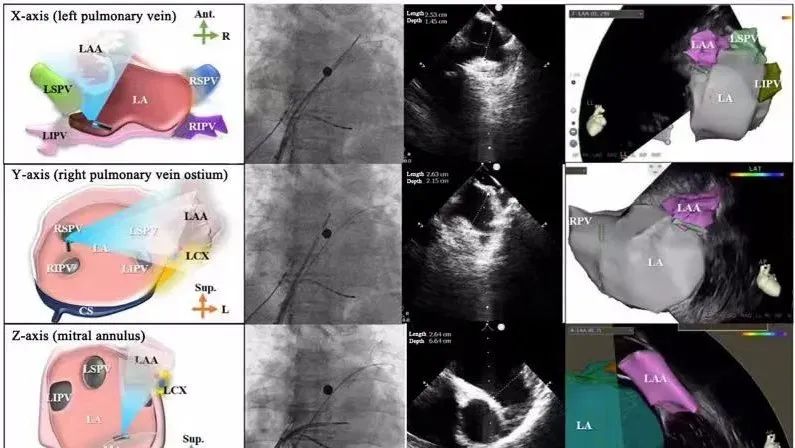

一種與心導(dǎo)管檢查相結(jié)合的超聲心動(dòng)圖診斷新興技術(shù),通過(guò)將超聲探頭置于心腔內(nèi)部,發(fā)射并接收超聲信號(hào),來(lái)精確獲取心臟解剖結(jié)構(gòu)、心臟血流動(dòng)力學(xué)等信息的實(shí)時(shí)成像。與其他影像技術(shù)相比,ICE技術(shù)具有操作簡(jiǎn)單、無(wú)輻射、安全性高、手術(shù)效率高、實(shí)用等優(yōu)勢(shì),ICE在很大程度上有望取代經(jīng)食道超聲心動(dòng)圖(TEE),成為電生理和結(jié)構(gòu)性心臟病領(lǐng)域的理想成像方式。

目前ICE技術(shù)已被應(yīng)用于左心耳封堵、房顫射頻消融、二尖瓣成形、房間隔缺損封堵等多種心臟介入手術(shù),應(yīng)用場(chǎng)景主要圍繞心臟電生理、結(jié)構(gòu)性心臟病等領(lǐng)域,目前以電生理應(yīng)用為主。數(shù)據(jù)顯示,我國(guó)結(jié)構(gòu)性心臟病介入器械市場(chǎng)規(guī)模已從2017年的4億元增長(zhǎng)至2021年的20億元,年復(fù)合增長(zhǎng)率達(dá)48.3%;預(yù)計(jì)到2025年,該市場(chǎng)規(guī)模將達(dá)到104億元,可以預(yù)見(jiàn)ICE市場(chǎng)規(guī)模也將同步高速增長(zhǎng),未來(lái)市場(chǎng)發(fā)展空間廣闊。

心腔內(nèi)超聲(ICE)技術(shù)壁壘極高,國(guó)內(nèi)主要廠商核心部件仍舊為進(jìn)口,集成了超聲和圖像處理最前端技術(shù),包括超聲探頭、線纜、軟件成像算法等,是當(dāng)前內(nèi)窺超聲方向最具挑戰(zhàn)的領(lǐng)域。ICE的應(yīng)用經(jīng)歷了2D平面成像、3D三維立體成像、以及4D的實(shí)時(shí)三維立體成像階段。